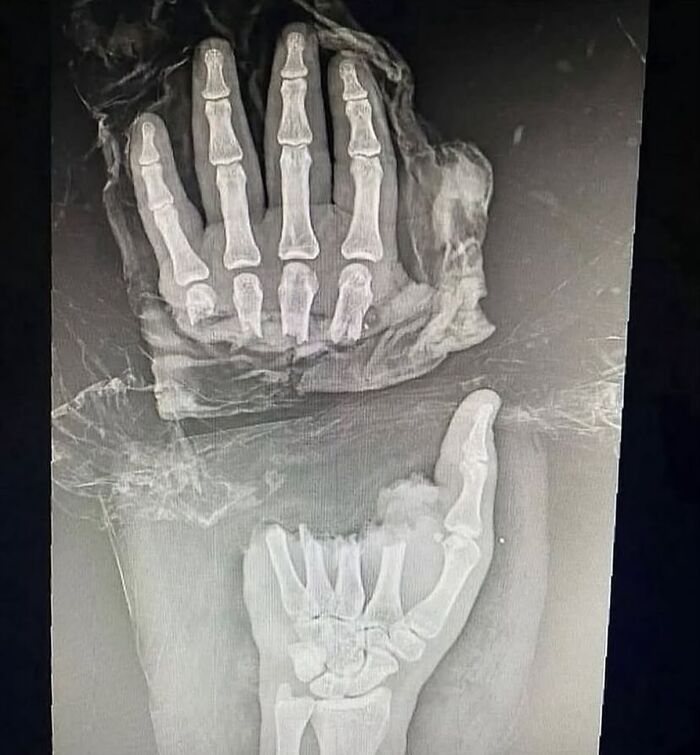

La radiografía simple de la articulación de la muñeca muestra polidactilia con duplicación del cúbito, duplicación de la cara cubital de los huesos del carpo, metacarpianos y falanges, ausencia de radio y ausencia del pulgar. Se observan ocho dedos trifalángicos. La falange media del dedo índice medial es hipoplásica.